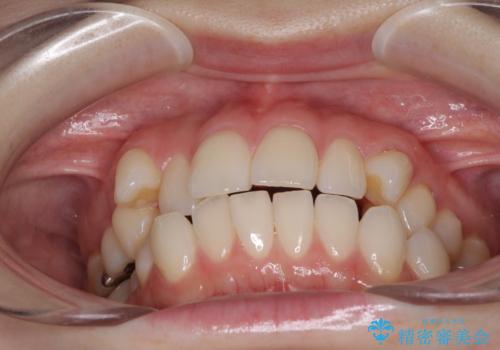

- 前歯のデコボコや八重歯の様になっていることを気にして来院された患者様です。

犬歯捻れて前方に飛び出しており、下顎前歯もそれに沿うようにデコボコとなっていました。

IPR(歯と歯の間を削る処置)によりスペースを獲得して上下顎前歯のデコボコを改善し、前歯が前方に突出しないように設定した上で、インビザラインにて矯正治療を行うこととしました。